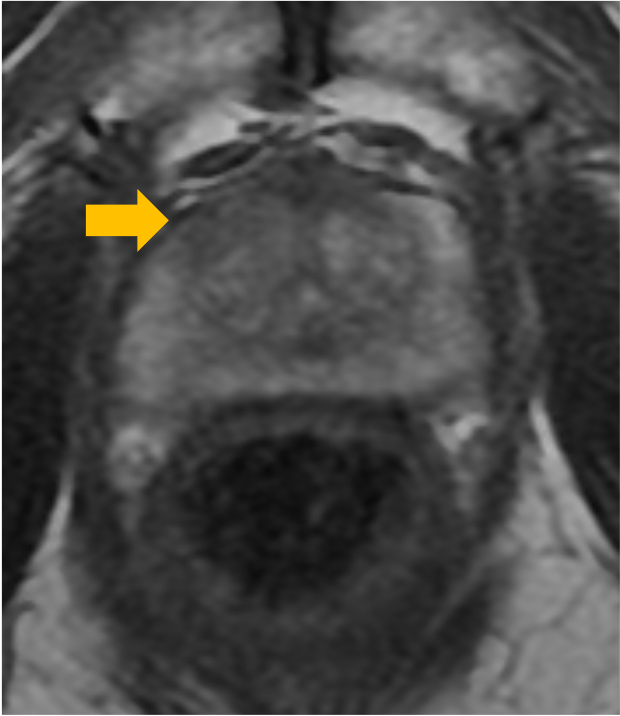

前立腺の系統的生検を以前に2回行うも癌の診断得られず。PSAが12.8まで上昇したため、ターゲット生検目的に造影MRIを撮像した。前立腺右葉移行域 11時方向に長径12mm大の病変を認め、T2強調画像で内部均一で境界不明瞭、レンズ状の低信号域(図1)、拡張強調画像で高信号(図2)、ADC map低信号(図3)、ダイナミック造影(75秒後)の結節状濃染(図4)を認めた。PI-RADSカテゴリーは4であった。

右葉移行域腹側を標的としたMRI-US fusion下ターゲット生検が行われた。3箇所よりGleason score (GS) 3+4=7, 4+5=9, 3+3=6 の検体が得られた。前立腺全摘術が施行され、病理診断では術前に指摘された病変を含め4箇所の腫瘍を認めた(図5)。右葉移行域腹側の病変が最大で径12x7mm大、GSは3+4=7であった。